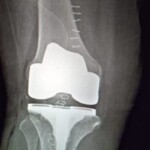

Computerised Knee Replacement

Use of computer during  knee replacement make it possible to place implant or prosthesis in perfect position and correct alignment which increase long term survival of implant or prosthesis and better function outcome.

1.Studies show that bone cuts can be made more accurate when guided by computer versus other systems

2.In Knee Replacement computer guidance eliminates the need for a rod to be placed inside the intramedullary (IM) canal of the bone. For the last two decades use of an IM rod has been the standard method of aligning cuts and has proved quite effective. Also it decreases the chances of Fat embolism.

3.With computer , ligament balancing can potentially be quantified to the nearest millimetre of ligament laxity or tautness., more precisely balance the ligaments of the knee.

4.The limb length equalization which is one of the greatest worries of the patient can be perfectly done